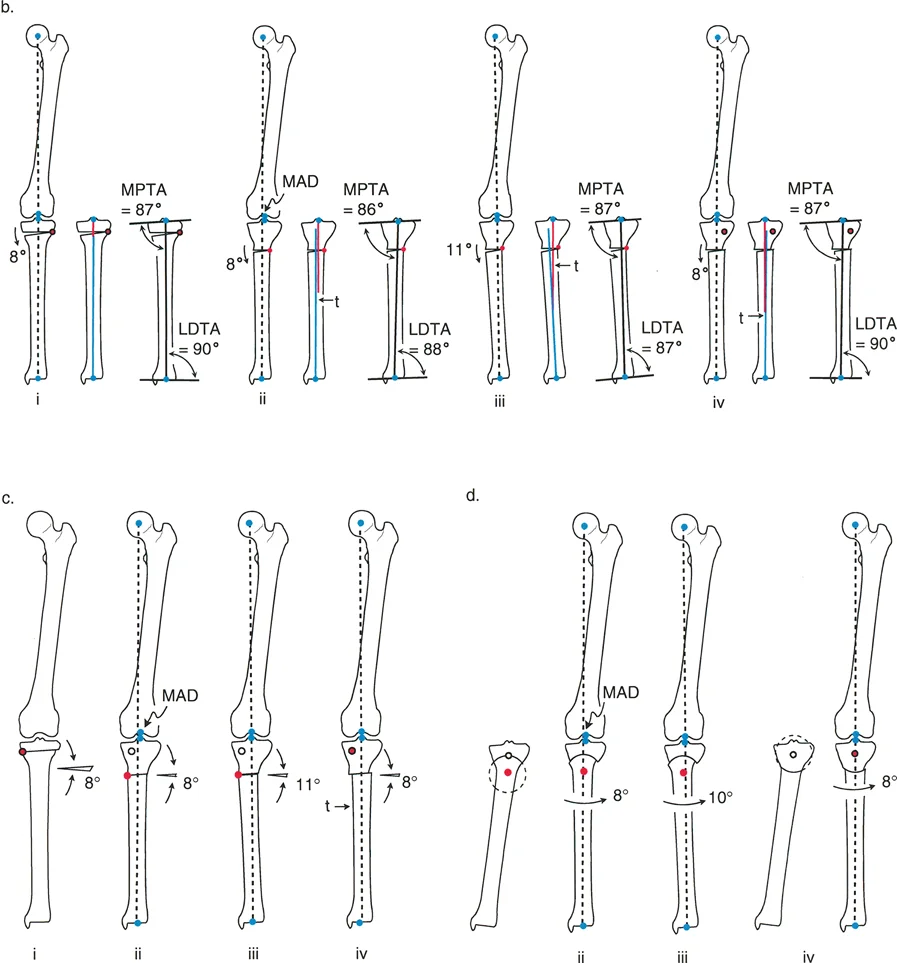

تقنيات قطع العظم المختلفة

هناك عدة طرق لقطع العظم، يختار الجراح الأنسب منها بناءً على نوع التشوه وشدته وموقعه:

إن نجاح جراحة تصحيح تشوهات الأطراف يعتمد بشكل كبير على التخطيط المسبق الدقيق. هذا التخطيط أشبه برسم خارطة طريق هندسية تضمن أن كل خطوة جراحية تقود إلى النتيجة المرجوة. يعتمد هذا التخطيط على "مبادئ بالي" التي تحدد ثلاثة متغيرات هندسية أساسية في كل حالة:

- مركز دوران التشوه (CORA - Center of Rotation of Angulation): هذه هي النقطة المحورية للتشوه في العظم. يحددها الجراح من خلال رسم محاور الطرف قبل الجراحة.

- محور تصحيح الزاوية (ACA - Angulation Correction Axis): هذه هي النقطة التي يدور حولها الجزء البعيد من العظم لتصحيح التشوه. يتحكم الجراح في هذه النقطة عن طريق وضع المفصلات على المثبت الخارجي أو نقطة الارتكاز للوحة التثبيت.

- مستوى قطع العظم (Osteotomy Level): هذا هو الموقع الفعلي الذي يتم فيه قطع العظم. يتحكم الجراح بشكل كامل في هذا المتغير، ويتم اختياره بناءً على عوامل مثل الأنسجة الرخوة، وجودة العظم، ونوع الأجهزة المستخدمة.

النتيجة النهائية للتصحيح تعتمد كليًا على كيفية ارتباط هذه المتغيرات الثلاثة ببعضها البعض. الفشل في التخطيط الدقيق يمكن أن يؤدي إلى "تشوهات ثانوية" غير مرغوب فيها، مثل انحراف المحور الميكانيكي أو ترجمة (إزاحة) العظم.